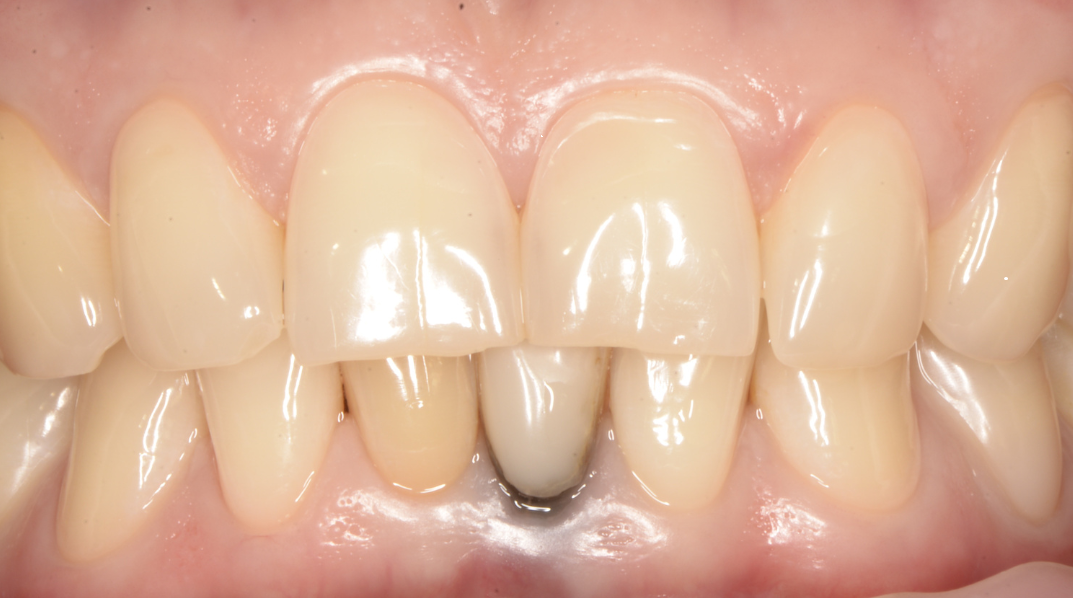

Складна негайна імплантація з кістковою пластикою

Олена, 30 років

Запальний процес у ділянці зуба внаслідок ускладненого карієсу та інфекції в кореневих каналах після перелікування. Значний дефект кісткової тканини з формуванням кістозного ураження та сполученням із гайморовою пазухою, що ускладнювало можливість негайної імплантації.